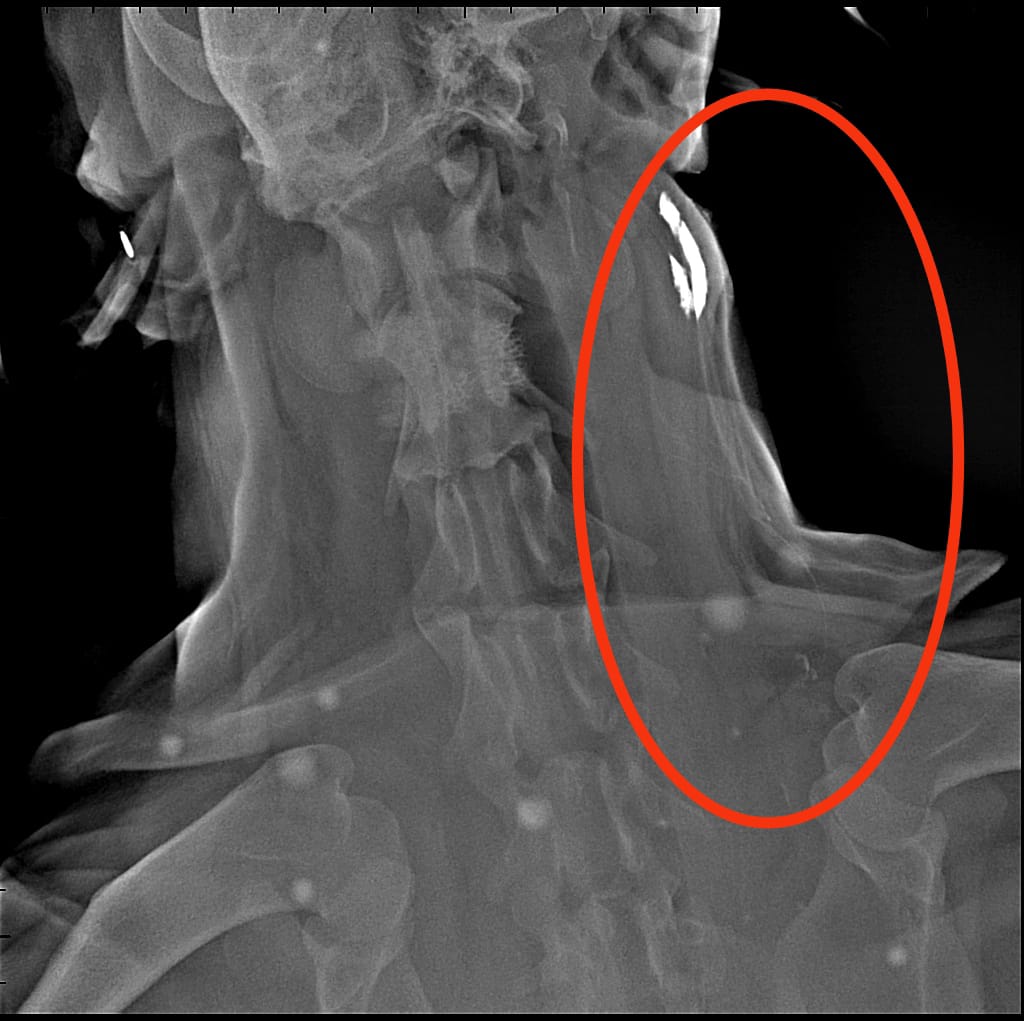

Il linfonodo regionale, ovvero il linfonodo che drena la linfa di quella determinata regione corporea, viene ricercato tramite l’inoculo perilesionale di una sostanza visibile all’esame radiografico (radiopaco). Dopo aver iniettato il mezzo di contrasto, sono state eseguite delle radiografie dopo 3, 6, 9 e 12 minuti: da queste è stato possibile osservare diversi “percorsi” del mezzo di contrasto che si portavano verso il linfonodo prescapolare.